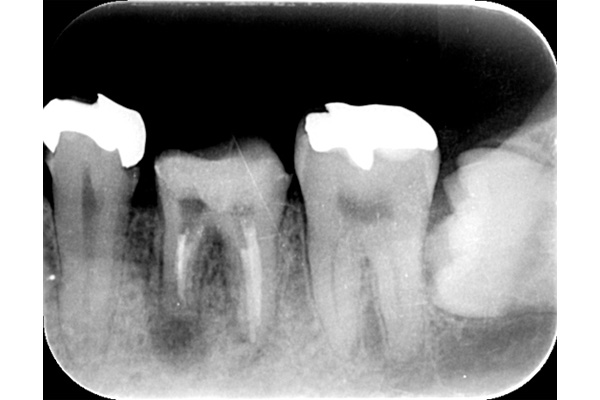

こちらの写真は違和感があるということでレントゲンを撮ったが異常は見つからなかった。しかし、1ヶ月後にもう一度撮影すると、歯が割れているのがわかりました。また、歯の周りの骨の部分がやや黒くなっているのも分かります。

ブリッジが取れたということでご来院患者様でした。レントゲンを撮ると縦に割れていました。

歯を抜くと、やはり割れていました。